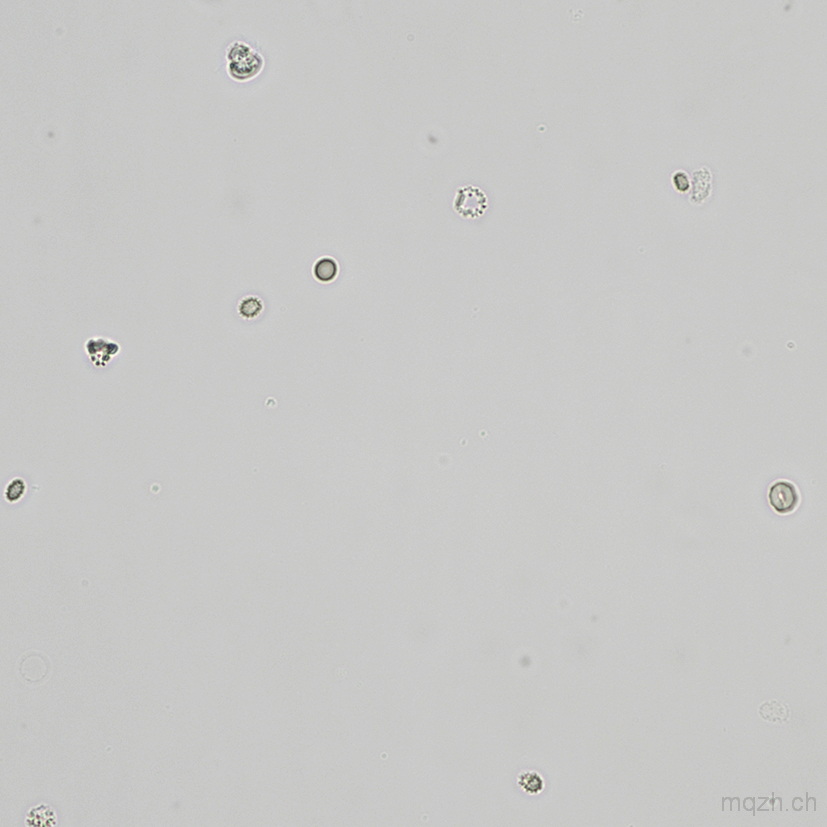

MQ 2025-4 Urinary Sediment U4